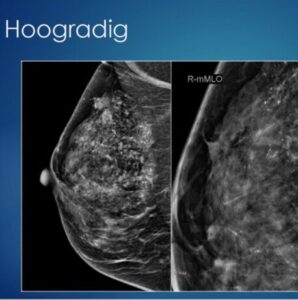

Waakzaam afwachten bij DCIS op korte termijn veilig

Nog voorziet het behandelprotocol bij laag-risico DCIS (Ductaal Carcinoma in Situ) in een borstsparende operatie. In de wetenschap dat de verdachte cellen zich in het overgrote deel van de gevallen niet tot invasieve borstkanker zouden ontwikkelen. Een …